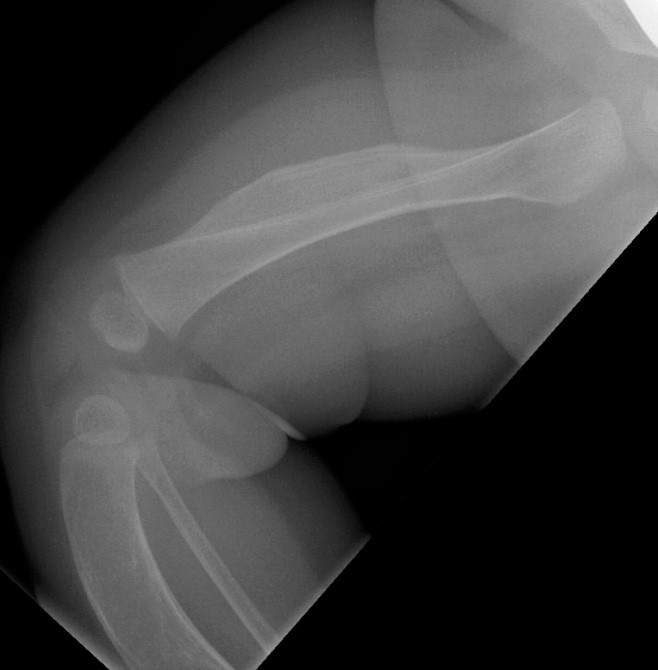

En tre måneder gammel jente ble henvist med spørsmål om tumor på låret. Barneradiolog fant ved ultralydundersøkelse distinkt ømhet og bløtvevsødem foran på høyre lår, men ingen bløtdelstumor. Supplerende røntgenundersøkelse viste fortykkelse av corticalis (kortikal hyperosteose) i høyre femurdiafyse (bildet til venstre), anterior krumming av begge tibiae med brede, oppdrevne diafyser og fortynnet corticalis. Tilsvarende forandringer ble funnet i høyre femur. Krumningen av tibia ses tydelig på lysbildet til høyre.

Pasientens far og farmor ble født med liknende legger – hos begge var det spontan bedring i løpet av et par år. Røntgenopptak av farens legger viste antydet anterior krumming av begge tibiae, med noe utvisket kortikomedullær grense i diafysene.

Sykehistorie og røntgenfunn var forenelig med Caffeys sykdom, infantil kortikal hyperostose, som er karakterisert ved subperiostal beinnydanning som oftest involverer mandibula, de lange rørknoklene, clavicula og ribbein.

Tilstanden debuterer typisk tidlig i spedbarnsperioden med feber, irritabilitet og lokal ømhet på grunn av bløtvevsødem (1). Tilheling skjer spontant i løpet av de to første leveårene. Leukocytose, forhøyet alkalisk fosfatase og forhøyet senkning ses ofte. Sykdommen nedarves autosomalt dominant. Den er en sjelden, men viktig differensialdiagnose til osteomyelitt, malignitet og barnemishandling.